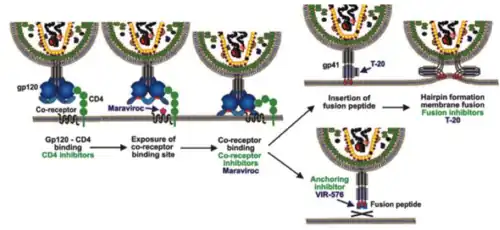

VIR-576 belongs to a kind of drugs categorized as antiretroviral, specifically it is an anchoring inhibitor that blocks HIV-1 entry into the host cell. It binds to a concrete hydrophobic fusion peptide called gp41, which is a transmembrane glycoprotein located in the retrovirus HIV-1 envelope.[2] Target cell interacts with the gp41 peptide in order to form a pre-hairpin structure which joins HIV-1 and host cell membranes.

Gp41 is exposed with the assistance of another glycoprotein (gp120) also located in the envelope of the retrovirus.[11] The structural reason is based on the fact that two gp41 combine with other gp120 composing a trimer.[12] Firstly, it interacts with the receptor CD4 of a T4 human cell (also called Th or helper lymphocyte). The fusion causes an increase of concentration of HIV-1 on the target cell’s surface, and that promotes a switch which increases the affinity of gp120 for chemokine receptors that are disposed onto the target cell surface. This interaction produces a conformational change in the glycoprotein gp120 that exposes gp41. This process would be active because VIR-576 does not interferes in this part of it, but when gp41 is exposed, the developed drug VIR-576 would commence its mechanism of action and the inhibition of the fusion would start to take place.

VIR-576 binding to gp41 inhibits the anchoring of the virus and the membrane fusion, and that means that the genetic controlling material of the retrovirus HIV-1 can not be introduced in the T4 lymphocyte. As a result, infection would not be initiated.

Differences from other antiretroviral drugs

VIR-576 mechanism of action differs from other drugs. Enfuvirtide (also known as T-20), for example, is a fusion inhibitor which binds to a region of the glycoprotein gp41 called HR1 in order to prevent membrane fusion.[13] While enfurtivide inhibits the formation of the hairpin which is able to trigger the membrane fusion, VIR-576 directly blocks the insertion inhibiting the anchorage which is the previous stage of the hairpin formation (because to develop the hairpin it is necessary the fusion and VIR-576 impedes it.[2]